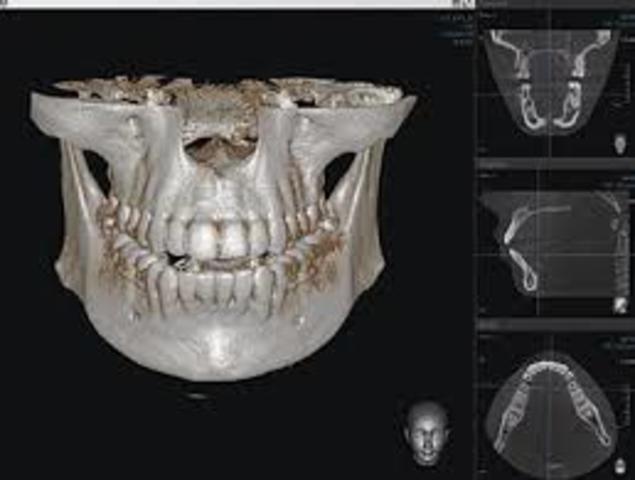

*Manejo de la imagen bidimensional –el radiológico–, o tridimensional –los demás–.

*Interfase de uso de los cuerpos tridimensionales bidimensional, en base a gráficos que representaban los cortes del objeto.

Tomógrafo de Haz Cónico (TCHC –Tomógrafo Computerizado de Haz Cónico–, o CBCT –Cone Beam Computed Tomography–), que se introdujo en 1997-1999 en Europa, con el NewTom,

*Expansión del CAD-CAM

*Radiología Digital Tridimensional.